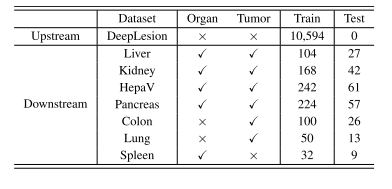

TABLE IOVERVIEW OF EIGHT DATASETS USED FOR THIS STUDY

表 1 本研究使用的 8 个数据集概述